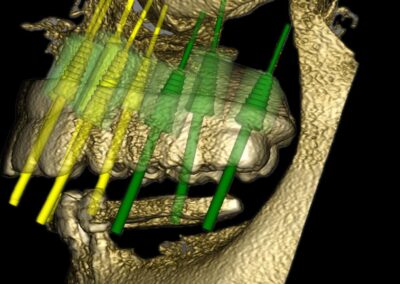

Vor der eigentlichen Operation können Implantatpositionen sorgfältig festgelegt werden, wobei spezifische Faktoren wie das Knochenvolumen und die -qualitäten, die Lage anatomischer Strukturen (wie Nerven, Gefäße und Nebenhöhlen), prothetische und ästhetische Bewertungen sowie präzise Messungen der Breite und Höhe des Knochens an den vorgesehenen Implantatstellen berücksichtigt werden. Auch die Abstände und Winkel zwischen den Implantaten lassen sich exakt berechnen, was entscheidend für den langfristigen Erfolg der Behandlung ist.

Ein weiterer Vorteil dieser Technologie ist die Möglichkeit der dreidimensionalen Positionierung der Implantate, die entscheidend für optimale klinische Ergebnisse ist, insbesondere in Bezug auf ästhetische Gesichtspunkte. Die geführte Implantatchirurgie (GIS) ermöglicht es, vorher geplante Rehabilitationsprojekte direkt und präzise in das chirurgische Feld zu übertragen. Dies fördert nicht nur die Genauigkeit, sondern kann auch dazu beitragen, eine minimal-traumatische oder lappenlose Operation durchzuführen.

Darüber hinaus erlaubt die GIS eine optimale Positionierung der Implantate und schafft die Voraussetzungen für eine sofortige Belastung. Dadurch wird nicht nur der Komfort des Patienten erhöht, sondern auch die Notwendigkeit von postoperativen Behandlungen und Schmerzen verringert.

Bilder v.l.n.r.: 01 Herstellung der röntgenopaken Schablone zur Übertragung auf den Dicom-Datensatz / 02 Planung der Zahnimplantatstellung anhand der röntgenopaken Schablone / 03 Virtuelle Planung auf dem 3D-Modell / 04 Übertragung der Röntgenschablone auf dem Dicom-Datensatz (1:1) / 05 Virtuelle Plaung im Dicom-Datensatz / 06 Visualisierung frontal / 07 Visualisierung seitlich / 08 Visualisierung des Implantat-Falles frontal / 09 Visualisierung mit Bohrschablone

3. Simulation und chirurgische Umsetzung

Moderne Planungssoftware erlaubt:

• Virtuelle Implantatinsertion

• Planung navigierter oder schablonengeführter Chirurgie

Die digitale Planung kann direkt in eine CAD/CAM-gestützte Bohrschablone überführt werden, wodurch die intraoperative Umsetzung hochpräzise erfolgt.